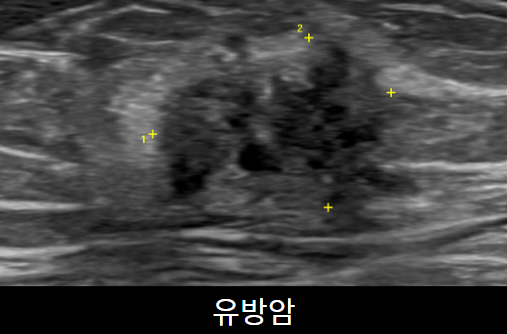

유방초음파

유방초음파 검사를 통해 유방낭종,염증, 종양을 진단할 수 있습니다. 유방촬영술과 같이 진행하는 것이 이 정확한 진단을 위해 필요합니다. 약 10~15분 소요됩니다.